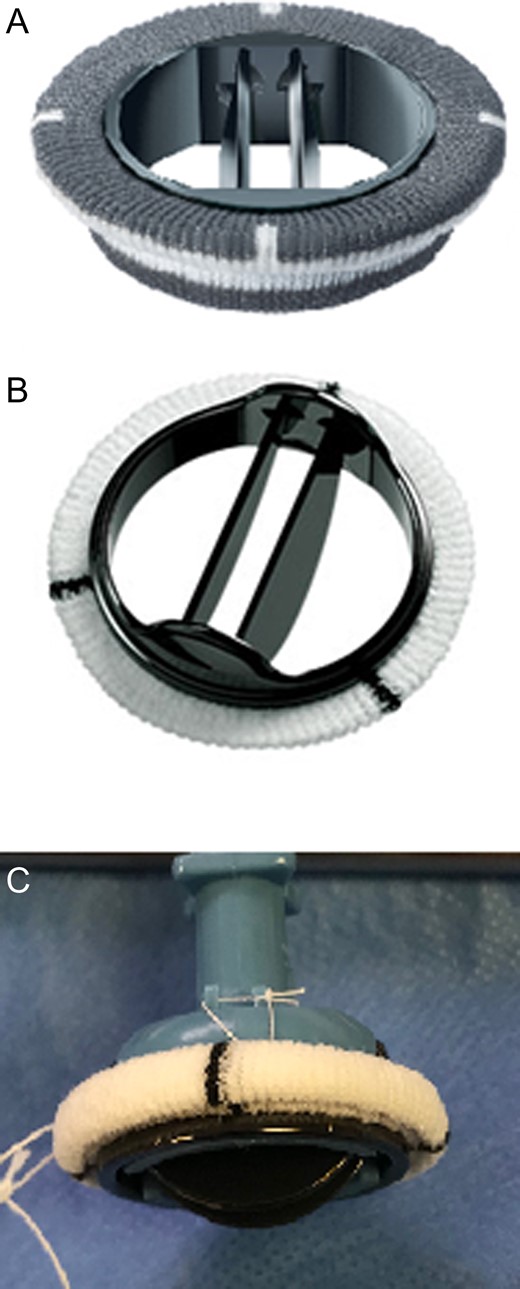

Examining the profile of each valve (Fig. 1), we believe the Carbomedics housing is more predisposed to cause obstruction than the St. Jude. The housing of the Carbomedics prosthesis extends more inferiorly than the St. Jude and potentially into the left ventricular cavity, impinging on the outflow tract. In a patient with coexisting septal hypertrophy, it is clear to see how these two factors alone could cause narrowing. As can be seen in the TTE slice in Fig. 2, the Carbomedics valve is protruding significantly into the LVOT. Severe LVOTO has previously been reported with a Carbomedics mitral valve which was subsequently relieved by replacing the prosthesis with a St. Jude valve [3].

Carbomedics mechanical mitral valve (A) and St. Jude mechanical mitral valve (B) and (C).